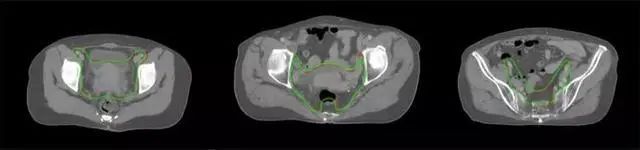

四、放射治療智能勾畫軟件

放射治療,簡稱放療,是治療腫瘤主要手段之一,利用放射線破壞照射區(qū)(靶區(qū))的細胞,使腫瘤細胞停止分裂直至死亡,醫(yī)生通常把放射治療形象的比喻為“打靶”,放療前精準勾畫腫瘤靶區(qū)范圍是腫瘤放射治療的關(guān)鍵步驟。傳統(tǒng)的靶區(qū)勾畫醫(yī)生會根據(jù)患者多張CT、MRI影像片憑借經(jīng)驗進行,比較耗時,治療的病人數(shù)量也有限,且靶區(qū)勾畫缺少行業(yè)統(tǒng)一的規(guī)范和標準,無法達到同質(zhì)化,勾畫精確度不理想。

技術(shù)原理

基于深度學(xué)習(xí)人工智能的放療靶區(qū)智能勾畫技術(shù)和自動計劃技術(shù),基于全面的市場調(diào)研和臨床專業(yè)意見,采用獨創(chuàng)的基于小樣本量的人工智能算法,實現(xiàn)放療靶區(qū)和危及器官的快速全自動勾畫。

產(chǎn)品優(yōu)勢

縮短至幾分鐘內(nèi)便可完成,大幅提升了放療效率,且人工智能平臺完成的靶區(qū)勾畫可基本滿足臨床醫(yī)生需求,專家只需審核時細微調(diào)整,可顯著提高靶區(qū)勾畫的規(guī)范化及精準度,讓放療智能化,標準化??筛采w食管癌、鼻咽癌、直腸癌、宮頸癌、肺癌等多種病種。